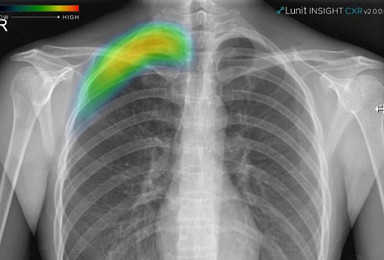

루닛, 폐 질환 검출 AI ‘루닛 인사이트 CXR 2’ 식약처 허가